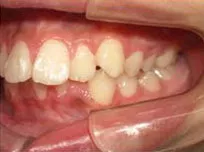

以下、当院で実施した床矯正の症例となります。

症例1

| 治療期間 | 11ヶ月(2021年6月〜2022年5月) |

| 費用 | 495,000円(税込) |

| リスクや副作用 | 成長期が終わった18歳以降に、2期矯正が必要になることがある |